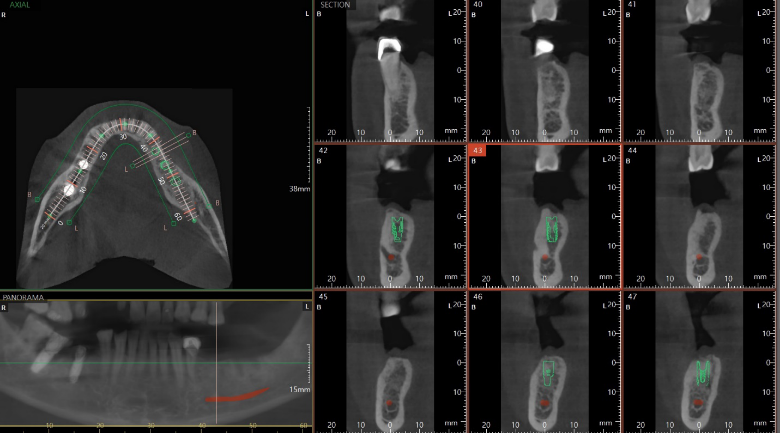

3D 컴퓨터 분석으로 명확한 임플란트 수술

역삼동임플란트 꼼꼼하고 명확하게 하는

저희 뉴엔은 치아 CT컴퓨터 단층촬영으로

3차원 입체영상으로 개인의 치아와 턱뼈의

폭, 높이, 신경과 같은 해부학적 구조를

잘 파악하여 보다 면밀하게 수술이

가능하도록 합니다.

이와 같은 방법을 통해 만성 질병을 가진 경우나

고령자에서도 안정적이며 세밀하게 수술하여

시간과 잇몸 절개의 크기, 수술 후 통증과

출혈 등을 크게 줄일 수 있습니다.